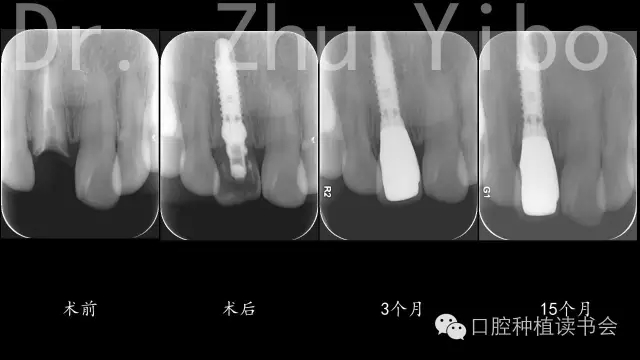

臨床檢查見:11殘根,松(-),齦(-),斷面齲壞,平齊牙齦齦,牙齦菲薄。21外翻(圖1)。術(shù)前根尖片及CBCT示:11根尖區(qū)低密度影,牙根腭側(cè)有橫向裂紋,唇側(cè)骨板薄,牙槽突與牙根長軸基本一致,符合一型分類(圖12、13)患者因時(shí)間、費(fèi)用問題,拒絕正畸治療,強(qiáng)烈要求即刻種植、即刻修復(fù)。

5、術(shù)后拍根尖片,確認(rèn)臨時(shí)冠就位良好(圖12)。

8、戴最終修復(fù)體,就位良好(圖12)。 術(shù)后1年復(fù)查,牙冠完好,牙齦美學(xué)評(píng)分14分(圖10、11)。

術(shù)前術(shù)后CBCT對(duì)比測量示:唇側(cè)牙槽骨穩(wěn)定(圖13)。術(shù)前術(shù)后石膏模型掃描,數(shù)字軟件重合對(duì)比測量:唇側(cè)牙齦組織穩(wěn)定(圖14)。